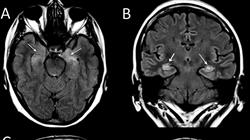

Die zukunftsträchtige Gruppe der entzündlichen und demyelinisierenden Erkrankungen des Nervensystems wird durch die Multiple Sklerose (MS) verkörpert. In diesem Programm werden die Syndrome und klinischen Muster demyelinisierender und entzündlicher Prozesse des ZNS, die verschiedenen Entwicklungsformen und wirksamen Diagnosemethoden untersucht, und es werden Behandlungsleitlinien in einem dynamischen und offenen Bereich der therapeutischen Forschung empfohlen. Eine einzigartige Gelegenheit für Mediziner, sich weiterzuentwickeln und zu wachsen.

Entzündliche und demyelinisierende Erkrankungen des Nervensystems sind komplexe Erkrankungen, die die Gesundheit und Funktion des zentralen und peripheren Nervensystems beeinträchtigen. Diese Krankheiten können erhebliche Auswirkungen auf die Lebensqualität der Menschen haben und erfordern ein gründliches Verständnis für die richtige Diagnose und Behandlung. Wenn Sie diesen Bereich eingehend erforschen möchten, hat die TECH Technologische Universität das ideale Programm für Sie. Der Universitätskurs in Entzündliche und Demyelinisierende Erkrankungen des Nervensystems ist ein Online-Aufbaustudiengang auf höchstem Niveau, der sich als einzigartige Qualifizierungsmöglichkeit präsentiert, um Ihre Fähigkeiten auf die nächste Stufe zu heben. Mit einem ganzheitlichen Ansatz werden wir die Ursachen, die zugrunde liegenden Mechanismen und die klinischen Manifestationen dieser Erkrankungen analysieren und Ihnen das nötige Handwerkszeug an die Hand geben, um diese Störungen zu verstehen und effektiv zu behandeln.

Im Laufe des Kurses, der von führenden Spezialisten von TECH entwickelt wurde, werden wir die wichtigsten entzündlichen und demyelinisierenden Erkrankungen des Nervensystems untersuchen, darunter Multiple Sklerose, akute disseminierte Enzephalomyelitis, Neuromyelitis optica und andere verwandte Erkrankungen. Sie werden die jüngsten Fortschritte in der Erforschung dieser Krankheiten sowie die innovativsten und vielversprechendsten therapeutischen Ansätze kennenlernen. Darüber hinaus werden Sie sich mit der Bedeutung eines multidisziplinären Ansatzes bei der Behandlung von entzündlichen und demyelinisierenden Erkrankungen des Nervensystems befassen. Am Ende des Kurses werden Sie mit einem soliden theoretischen und praktischen Wissen auf diesem Gebiet ausgestattet sein. Ganz gleich, ob Sie sich für die Forschung, die klinische Praxis oder die Patientenversorgung interessieren, dieser Kurs wird den Grundstein für Ihre berufliche Entwicklung in diesem faszinierenden Bereich legen.